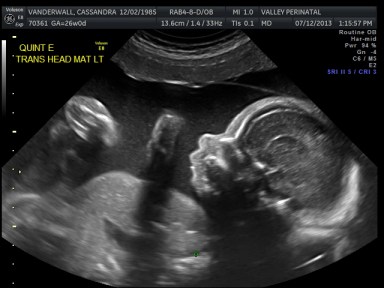

Friday we surpassed yet another milestone! The babies have been cooking for 7 months, which means we are now above the average gestational age for quintuplets. All of the babies were measured on Friday and they are all measuring within a day or two of the recommended size for babies at this point in pregnancy.

The weight of each baby is estimated based on the length of the baby’s humerus (bone in upper arm) and femur (bone in upper leg), the circumference of their abdomen and their head circumference.

The biggest one in the bunch is Baby B at 2lbs and 12oz at the 62nd percentile. Little Elle Rose (Baby E) is the munchkin, but not by much as baby D and Theo (baby A) are also the same weight (2 ½ lbs) but just a bit longer. At this rate, when the baby’s are measured again at 32 weeks they will be about 1lb heavier each. Let’s just hope this Mama can keep up!

All of their organs (kidneys, bladders, hearts, brains, stomachs) look great and are also appropriate sizes. The blood flow to Elle has improved and has stabilized. All heart rates remain within normal limits, and are often on the higher side, which is probably because they just can’t sit still. We are truly excited to meet our little wiggle worms!